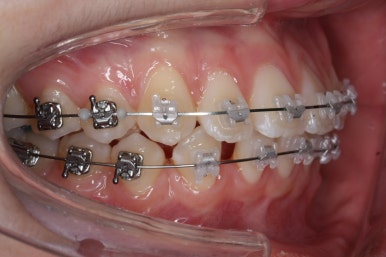

점점 단계가 진행될수록 얼굴의 중앙~윗니의 중앙~아랫니의 중앙이 점점 맞아가고 있음을 알 수 있습니다.

위아래 중앙도 어느 정도 맞아가고 있고, 발치를 한 자리와 결손치아 부위의 틈도 거의 없어져 가고 있습니다.

부산교정 키다리아저씨치과에서는 이번 환자분은 아래 앞니를 3개로 마무리하는 것이 아니라 송곳니를 끌어 당겨와서 앞니처럼 마치 앞니가 4개 있는 것처럼 마무리를 할 계획이어씨 때문에 정면에서 바라보았을 때 앞니 하나가 없는 느낌이 없이 어느 정도 중앙을 맞출 계회이였고, 원할히 진행되고 있음을 알 수 있습니다.

큰 그림은 거의 다 완성되었고, 디테일한 마무리 과정을 거친 후 치료를 종료하게 됩니다.